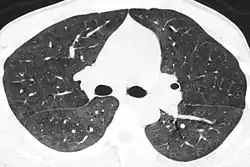

Диагноз устанавливается на основании данных рентгенографии и, предпочтительно, компьютерной томографии, демонстрирующей картину диффузных или диффузно-мозаичных зон снижения воздушности лёгочной ткани по типу «матового стекла». На этом фоне оксигенация артериальной крови значительно ниже ожидаемой при наблюдающейся клинической картине. Диагноз подтверждается обнаружением предполагаемого патогена в мокроте или при исследовании бронхоальвеолярного смыва. При микроскопии окрашенного материала обнаруживаются характерные кисты[5], имеющие вид «раздавленных шариков для пинг-понга». При микроскопии биоптата лёгкого выявляется утолщение альвеолярных перегородок с «пушистым» эозинофильным экссудатом в просвете альвеол.